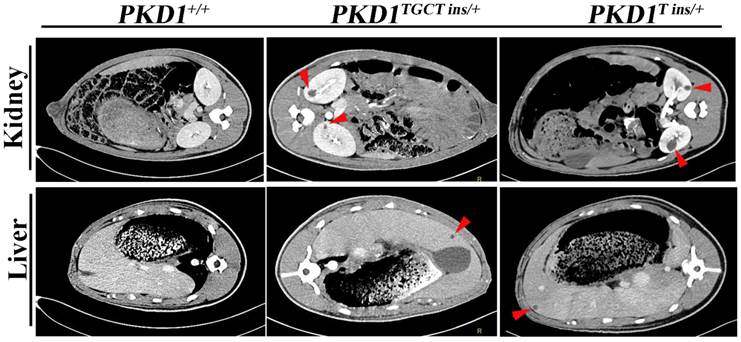

As an accurate approach for detecting renal cysts, contrast-enhanced computed tomography (CT) was employed to examine the 11-month-old pigs. To our knowledge, there is no CT diagnostic criterion for ADPKD; thus, we adopted an ultrasonographic standard to examine these pigs [25]. In this criterion, the presence of at least 3 cysts in one or two kidneys from patients younger than 30 years of age would confirm the diagnosis of ADPKD. Because contrast-enhanced CT can detect a cyst of at least 1.5 mm, we set the threshold to 5 mm for counting cysts to minimize the false-positive diagnosis. We found that many different-sized cysts were present in the bilateral kidneys of all tested PKD1+/- pigs (Fig. 3 and Supplementary Material: Table S5). Means of nine and five cysts in bilateral kidneys of the 11-month-old pigs had larger diameters than 5 mm in the PKD1TGCT ins/+ and PKD1T ins/+ pigs, respectively. The largest diameter was 28.3 mm in a PKD1TGCT ins/+ pig, while a PKD1T ins/+ pig had a 19.3 mm cyst. In addition to renal cysts, liver cysts, observed in approximately 80% of ADPKD cases [26], were found in all PKD1+/- pigs (Fig. 3).

Figure 3

Contrast enhanced computed tomography was performed to diagnose the renal and hepatic cysts in PKD1+/- pigs at 11-month-old. Red arrowheads show the typical cysts in the kidneys and livers.